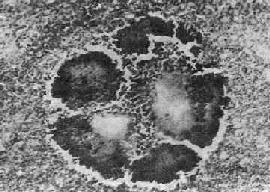

图18-36 放线菌病

病灶中的“硫黄颗粒”,周围部分菌丝排列成放线状。菌丝末端膨大呈棒状

放线菌病和病变为慢性化脓性炎症。局部组织水肿,有大量中性粒细胞和单核细胞浸润,其间逐渐出现许多大小不等的坏死区,形成多数小脓肿,周围纤维组织增生。脓肿大小不等,常相互融合,并向邻近组织蔓延,形成许多窦道和瘘管。脓肿壁和窦道周围肉芽组织内有大量中性粒细胞、淋巴细胞和单核细胞浸润,有时并有少数多核巨细胞,部分可见大量吞噬脂类的巨噬细胞,因此肉眼观常带黄色。放线菌在脓肿壁、窦道壁和脓腔内繁殖,形成菌落。有时肉眼可见脓液内有细小的黄色颗粒,直径约1~2mm,称为“硫黄颗粒”。取硫黄颗粒直接压片或在组织切片中可见颗粒由分支的菌丝交织而成。在HE染色的组织切片中,颗粒中央部分染蓝紫色,周围部分菌丝排列成放线状,菌丝末端常有胶样物质组成的鞘包围而膨大呈棒状,染伊红色,所以称为放线菌(图18-36)。